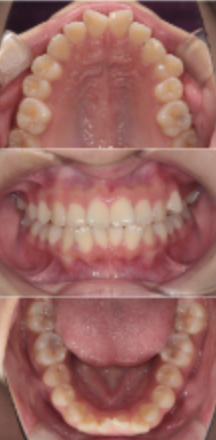

今回は、15歳の女性患者さんの矯正治療症例をご紹介します。

この症例は、単に歯並びを整えるだけでなく、顎関節の問題と咬合(かみ合わせ)を最優先に考えた治療が必要だったケースです。

矯正相談時の主訴と初診時の状態

患者さんが矯正相談に来院されたのは15歳の時。

主なご相談内容は「歯並びが気になる」という一般的なものでしたが、診察を進めていく中で、いくつかの重要な問題が見つかりました。

② 犬歯(3番)の著しい咬耗

さらに注目すべきだったのが、上下左右すべての犬歯(3番)が強くすり減っていた点です。

通常、犬歯は「ガイド」として噛み合わせを守る非常に重要な歯ですが、本症例では歯軋り(ブラキシズム)によると考えられる明らかな咬耗が認められました。

2年半の矯正治療を経て

矯正装置を装着してから、治療期間は約2年半。

治療終了時には、

-

歯列はきれいに整い

犬歯誘導が回復

噛み合わせも安定

顎関節のクリック音もほぼ消失

という、機能面・審美面ともに非常に良好な結果を得ることができました。